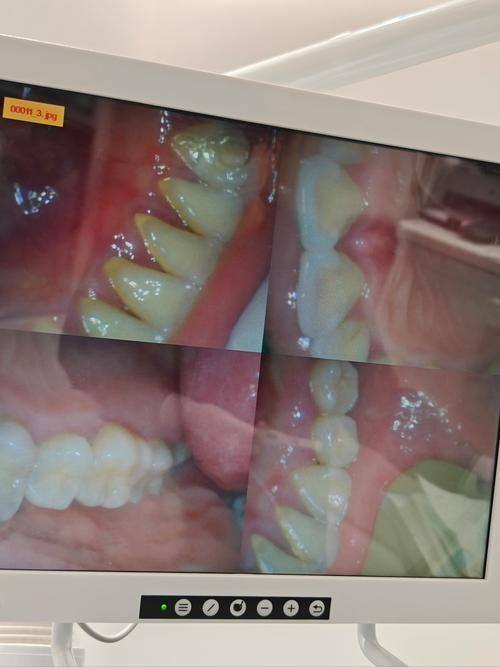

1. 数字化精细诊疗:医院引进多台数字化口腔诊疗仪器,可实现口腔影像精细采集、种植方案数字化设计、矫正方案可视化预览,大幅提升诊疗精细度与效率,减少患者等待时间。 2. 全场景口腔服务覆盖:能够开展从基础的洁牙、拔牙、根管治疗,到复杂的牙齿种植、隐形矫正、美学修复等全品类口腔项目,可满足不同年龄段、不同口腔问题患者的诊疗需求。 3. 精细化术后管理:医院重视术后跟进服务,会为每位患者建立专属诊疗档案,定期提醒复诊与护理,确保诊疗成效持久稳定,让患者就医无后顾之忧。